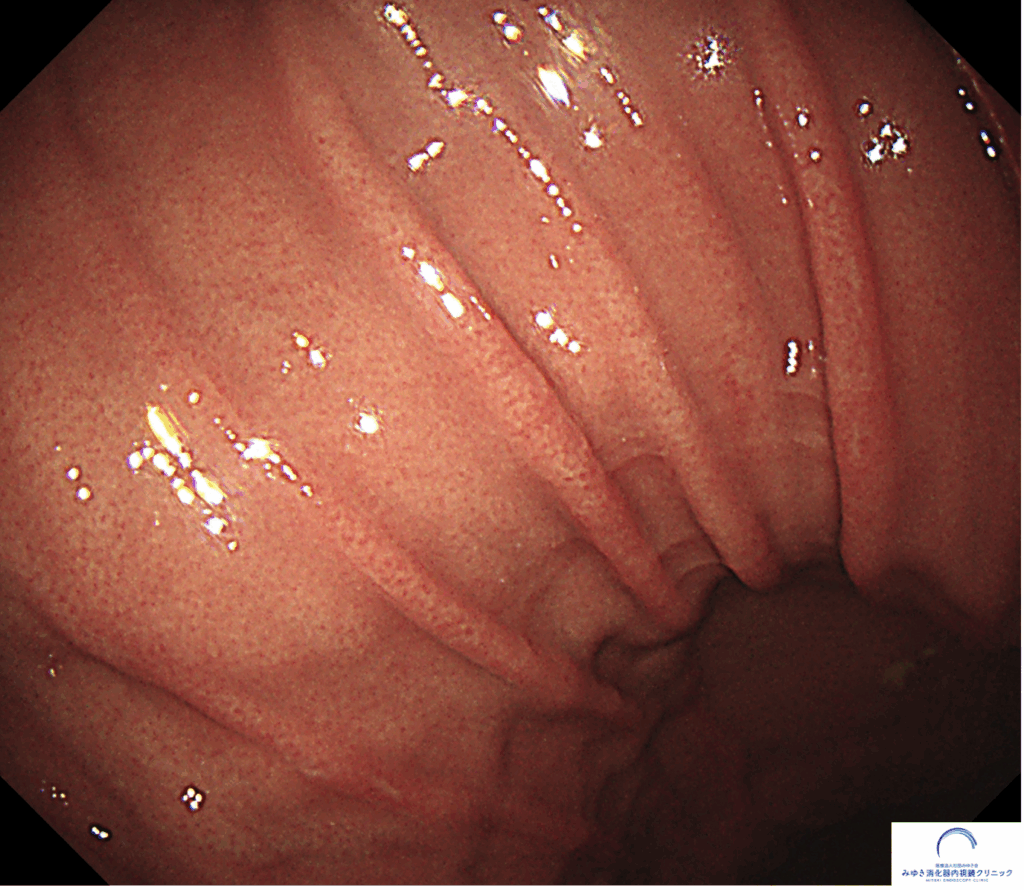

*参考までに正常な胃の写真です。ひだの太さと胃の広がり方が違うのが一目瞭然です。